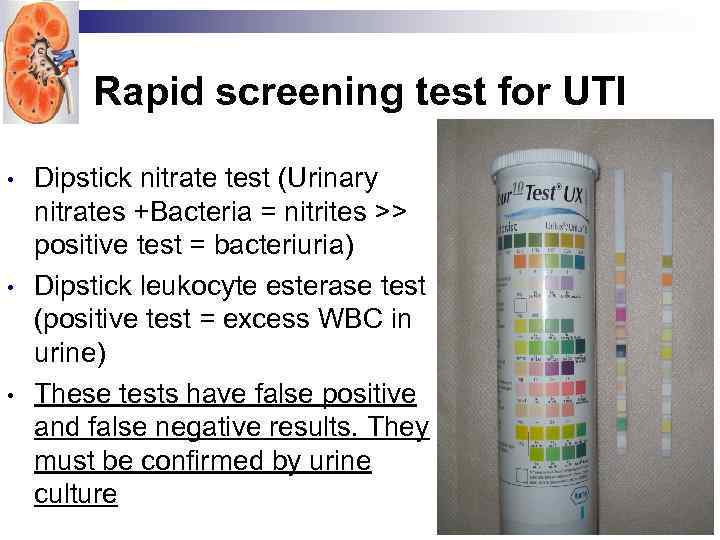

Rapid screening test for UTI • • • Dipstick nitrate test (Urinary nitrates +Bacteria = nitrites >> positive test = bacteriuria) Dipstick leukocyte esterase test (positive test = excess WBC in urine) These tests have false positive and false negative results. They must be confirmed by urine culture

Rapid screening test for UTI • • • Dipstick nitrate test (Urinary nitrates +Bacteria = nitrites >> positive test = bacteriuria) Dipstick leukocyte esterase test (positive test = excess WBC in urine) These tests have false positive and false negative results. They must be confirmed by urine culture